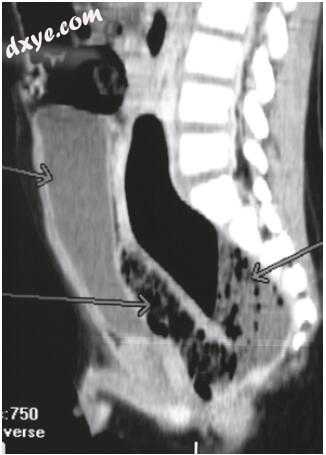

图37.2.5。一个5岁男孩的CT腹腔矢状体重建术被错误地治疗了急性阑尾炎,后来发现其直肠后部穿孔较大,并有直肠后集合体,这是“传统灌肠”的并发症。左箭头指出了膀胱和直肠,而右侧箭头所指的是直肠后方的大型充气结构